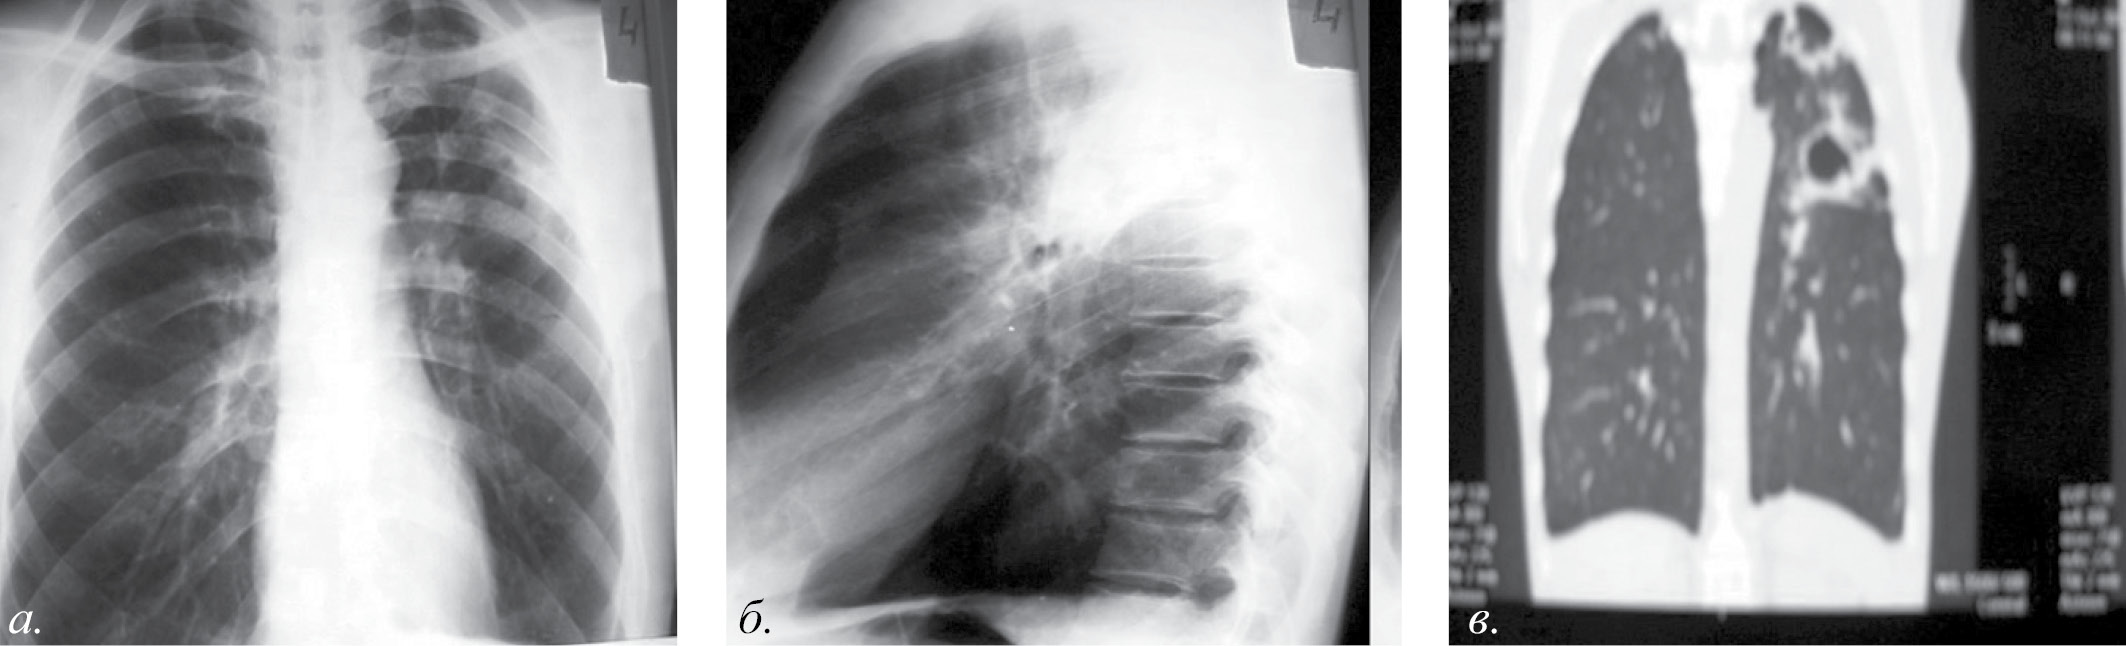

В сентябре при появлении кровохарканья больной повторно госпитализирован в ЦРБ с диагнозом пневмония (рис. 1 – а, б, в).

Рис. 1. Центральный эндобронхиальный рак верхнедолевого бронха слева с переходом на главный бронх, метастазы в лимфатические узлы средостения (а – рентгенограмма органов грудной полости в прямой проекции; б – рентгенограмма в боковой проекции; в – МСКТ-изображение во фронтальной реконструкции)